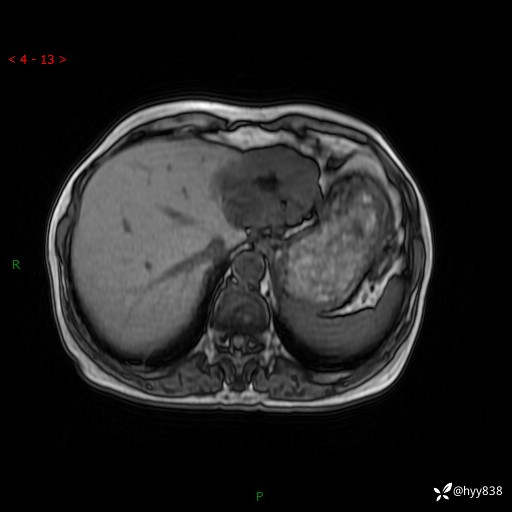

肝脏MRI平扫(同反相位)

增强(动脉期+静脉期+延迟期)